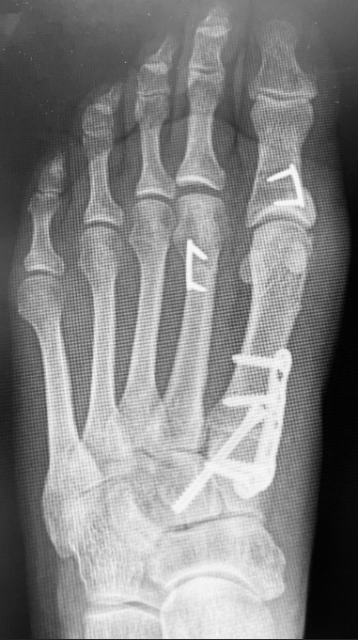

The dorsal chevron osteotomy is our preferred technique in patients whose primary pathology is metatarsal parabola disruption, with minimal digital deviation. Its V-shaped geometry provides intrinsic transverse-plane stability, and because the osteotomy takes place in the metatarsal neck, the MTPJ capsule can largely remain intact—limiting soft-tissue morbidity.

Surgical Technique. The surgeon makes a longitudinal incision over the target metatarsal, or between rays if addressing multiple metatarsals. Retraction of the extensor tendon is next, as lengthening only occurs when necessary to correct deformity. Dissection proceeds to the periosteum while maintaining capsular integrity.

Using a small precision sagittal saw blade, one plans the chevron osteotomy >4 mm proximal to the dorsal capsule/articular surface. The orientation of the osteotomy must accommodate planned fixation, as one must have adequate space far enough away from the articular surface for the placement of the distal dorsal staple arm. Creation of the medial and lateral wings takes place perpendicular to the metatarsal shaft, converging centrally in the neck.

Once the surgeon mobilizes the capital fragment, they can achieve controlled shortening by resecting a parallel wedge proximally. Fluoroscopy can confirm metatarsal length; we recommend incremental bone removal to the desired amount of shortening.

Fixation typically consists of a single 10-mm dorsal staple. The chevron geometry provides transverse plane stability, while the staple offers reliable sagittal plane control. In our experience, this combination has prevented floating toe and dorsal stiffness and has allowed early weightbearing in a surgical shoe.

Indications

• Parabola disruption requiring precise in-line shortening

• Minimal transverse-plane digital deformity

• Desire to preserve MTPJ soft tissues

• Need for a stable construct that tolerates early weightbearing

The dorsal chevron osteotomy offers controlled axial decompression, inherent transverse-plane stability, early weightbearing, and preservation of the MTPJ capsule—features that have contributed to our absence of floating toe in this cohort.